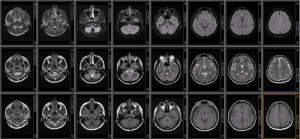

Mapping Myelin Content With MRI: Existing and Emerging Methods

Jon-Fredrik Neilsen, Ph.D., Navid Seraji-Bozorgzad, M.D., and Amaya Murguia